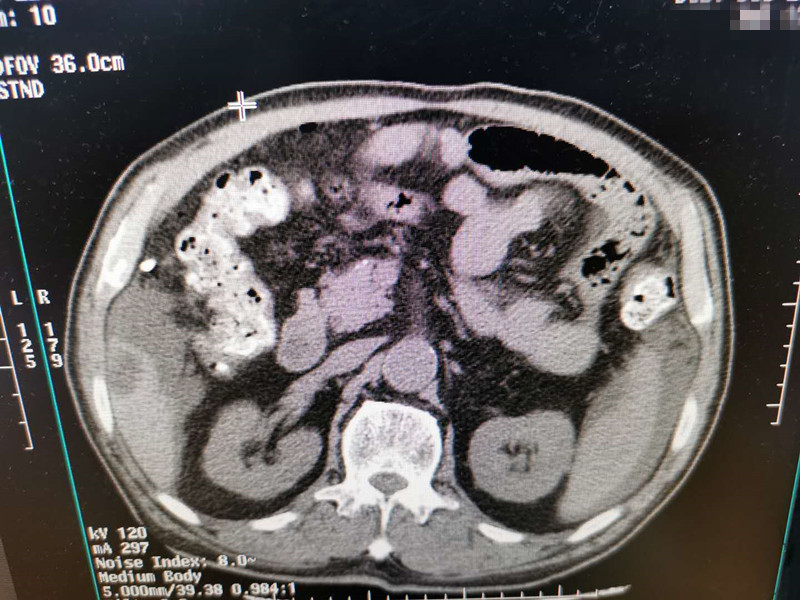

83岁肺部氩氦刀冷冻消融